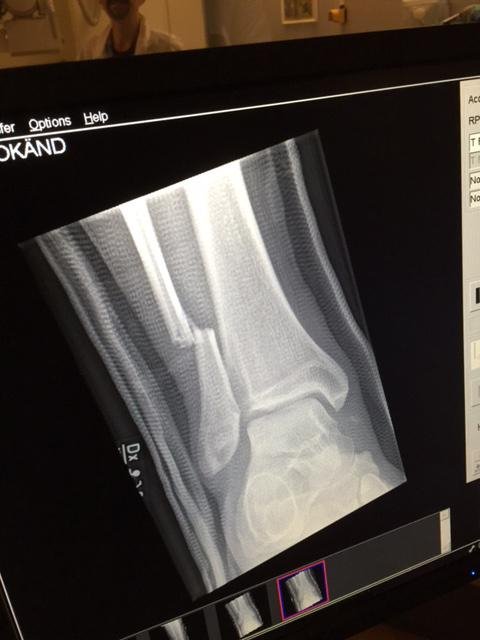

Μάλιστα, στο λογαριασμό του συγκροτήματος στο Twitter αναρτήθηκε και η ακτινογραφία του Γκρολ